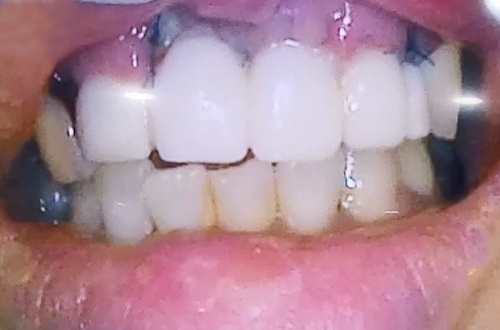

앞니 치아가 여러 개 빠진 상태의 임플란트 사례

BEFORE

AFTER

넘어지면서 앞니 치아가 여러 개 빠진 환자분이십니다.

첫번 째 앞니와 두 번째 앞니, 오른쪽 앞니가 빠진 상태로 방문하셨는데

오른쪽 두 번째 치아의 경우에도 많이 흔들리고 주변의 잇몸뼈들이

으스러져 있는 상태였기 때문에 두 번째 앞니까지 발치한 뒤

임플란트 2개로 치아 4개를 동시에 만들어 주는 치료를 계획하여 진행해드렸습니다.

당일 즉시 임플란트 수술을 진행하면서 뼈이식을 통해 단단하게 보강해 준 뒤

즉시 식립을 진행하고 임시치아를 만들어드리며 치료를 마무리하였습니다.